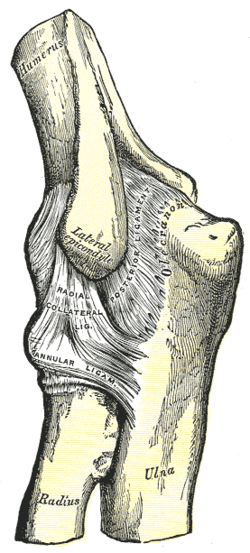

Left: anterior and ulnar collateral ligaments

Right: posterior and radial collateral ligaments

The elbow, like other joints, has ligaments on either side. These are triangular bands which blend with the joint capsule. They are positioned so that they always lie across the transverse joint axis and are, therefore, always relatively tense and impose strict limitations on abduction, adduction, and axial rotation at the elbow.[7]

The ulnar collateral ligament has its apex on the medial epicondyle. Its anterior band stretches from the anterior side of the medial epicondyle to the medial edge of the coronoid process, while the posterior band stretches from posterior side of the medial epicondyle to the medial side of the olecranon. These two bands are separated by a thinner intermediate part and their distal attachments are united by a transverse band below which the synovial membrane protrudes during joint movements. The anterior band is closely associated with the tendon of the superficial flexor muscles of the forearm, even being the origin of flexor digitorum superficialis. The ulnar nerve crosses the intermediate part as it enters the forearm.[7]

The radial collateral ligament is attached to the lateral epicondyle below the common extensor tendon. Less distinct than the ulnar collateral ligament, this ligament blends with the annular ligament of the radius and its margins are attached near the radial notch of the ulna.[7]